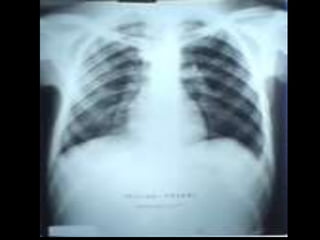

C’est un téléthorax de face objectivant une volumineuse opacité de

tonalité hydrique hilaire gauche Forme : grossièrement ovalaire

Taille : mesure 6 à 8 cm de grand axe

Limites : interne noyée dans le médiastin et se raccordant à angle aigue

avec le bord gauche du médiastin.

Limite externe flou irrégulière réalisant l’aspect en patte de crabe

Plage : hétérogène par la présence de broncho gramme aérien

Index cardio thoracique, les culs de sacs pleuraux sont libres

On note une petite opacité de tonalité calcique se projetant sur le lobe

supérieur du poumon droit

Conclusion : gros hile tumorale malin gauche évoquant un cancer

bronchique proximal

Pas de diagnostic différentiel

CAT : bilan d’extension:fibroscopie bronchique, TDM thoracoabdominale, échographie abdomino-pelvienne et scintigraphie osseuse